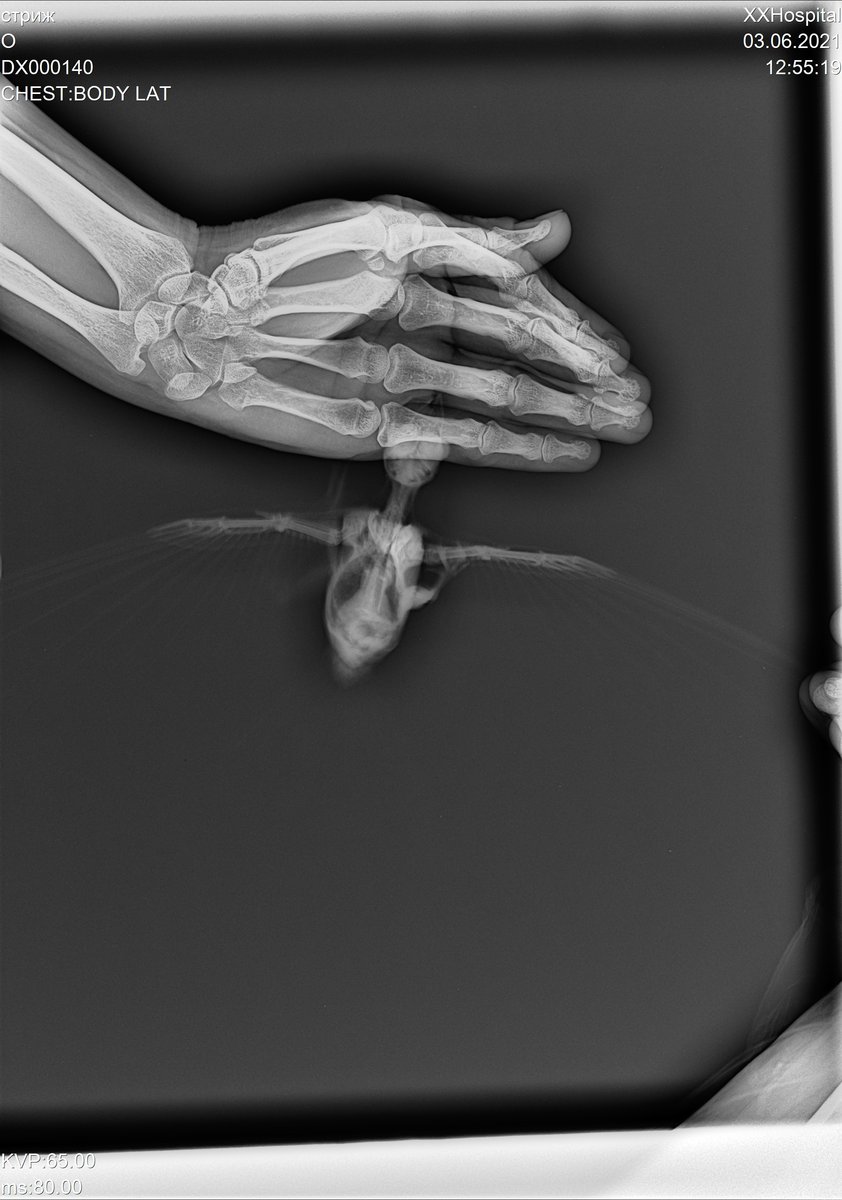

сделали ренген стрижу, только специалистов по птицам в клинике нет.. хотя бы знать нет ли  ничего серьезного.. ехать в москву нет возможности.

DX000140_3.jpg

@валена простите, не видела раньше вашу тему. Что-то с оповещениями не то. К сожалению, по данному рентгену можно очень мало чего сказать. Он совершенно бездарен.

Разве что если переделать? Стрижа для снимка кладут на спинку и полностью  раскрывают его крылышки. Нужен только 1 снимок.